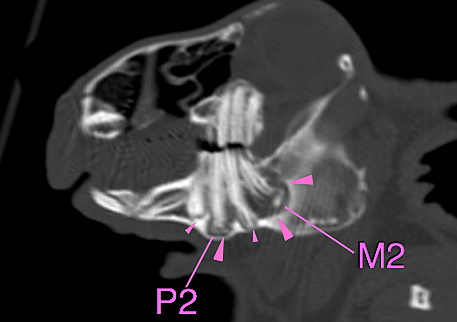

基本的には切歯を肉眼で観察し、口の中に耳鏡などを入れて臼歯を観察します。ただし目視で観察できるのは歯肉から出ている歯冠のみで歯根は見れません。

歯根はX線検査をで評価をしますが、左右、上下が重なっての評価になり、全ての異常を確認することはできません。

正確に診断するにはCT検査が必要になります。ウサギは無麻酔で撮影が可能です。